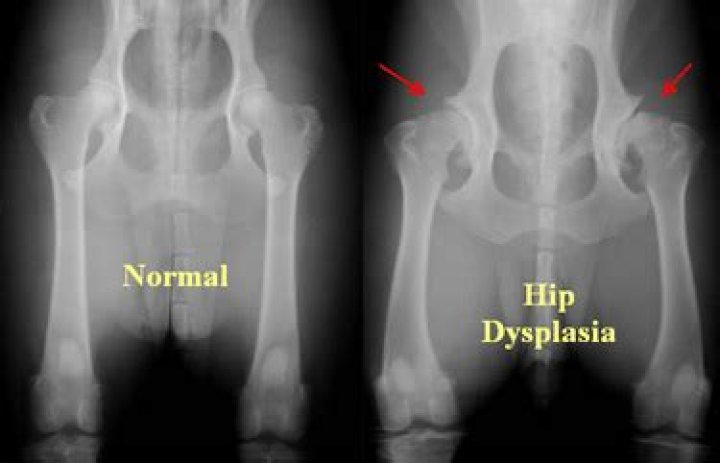

In dogs, hip dysplasia is an abnormal formation of the hip socket that, in its more severe form, can eventually cause crippling lameness and painful arth...